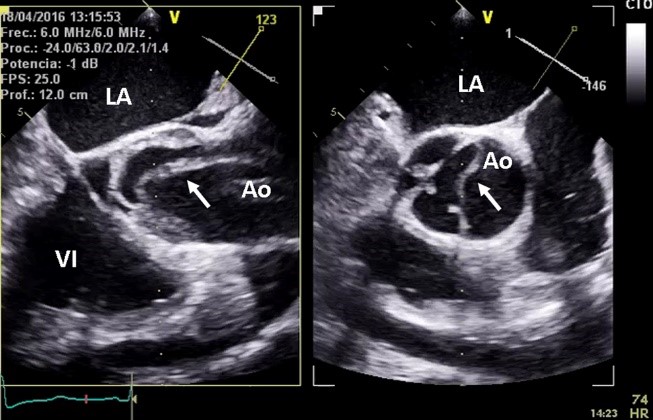

Hình 3: Siêu âm tim qua thành ngực (trái),

siêu âm tim qua thực quản (phải) cho thấy hình ảnh của nội mạc bung ra khỏi

thành động mạch chủ (mũi tên)